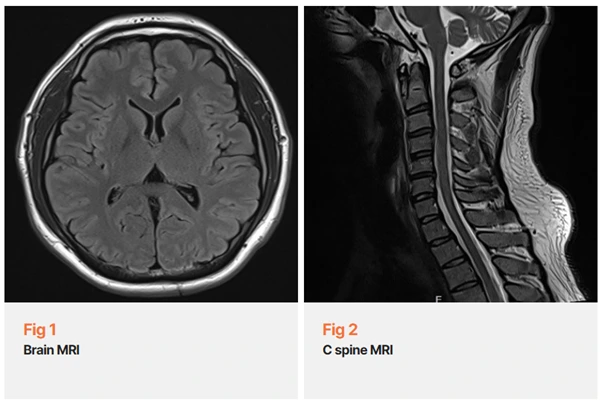

솔직히 말씀드리면, 눈 떨림이 1주일 이상 지속되는 경우에는 저도 먼저 당일 뇌 MRI를 권유해요.

뇌신경이나 중추신경계 이상 가능성을 먼저 배제해야 하거든요.

환자분도, 보호자도, 저도 그걸 가장 먼저 확인해야 안심이 되니까요.

다행히 뇌 영상 검사에서는 특이 소견이 없었습니다.

그런데 저는 거기서 멈추지 않았어요.

두통의 양상이 후두부와 측두부 쪽이었고, 눈 떨림이 동반된 점이 마음에 걸렸거든요.

목 MRI를 함께 확인했을 때, 상부 경추에서 기능 장애 소견이 보였어요.

바로 이 부분이 핵심이었어요.